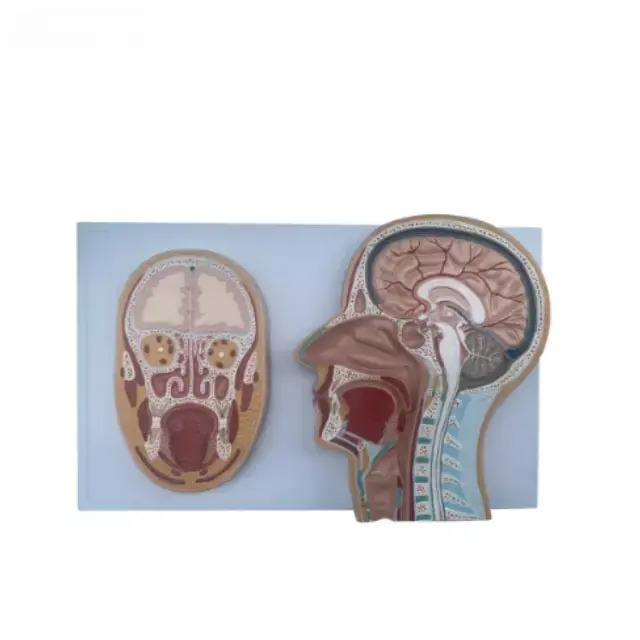

Sección Frontal Media de la Cabeza Serie

Descripcion general